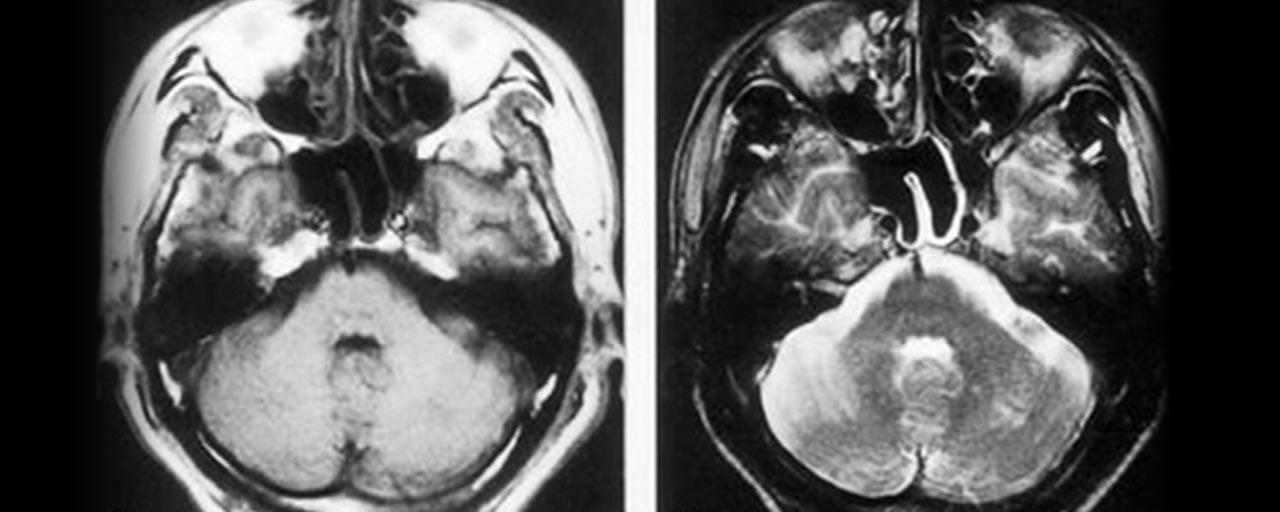

画像所見はMRIでT1画像で動脈壁の三日月状高信号(壁在血栓)やMRAで

pearl and strings signやflap形成が見られる。